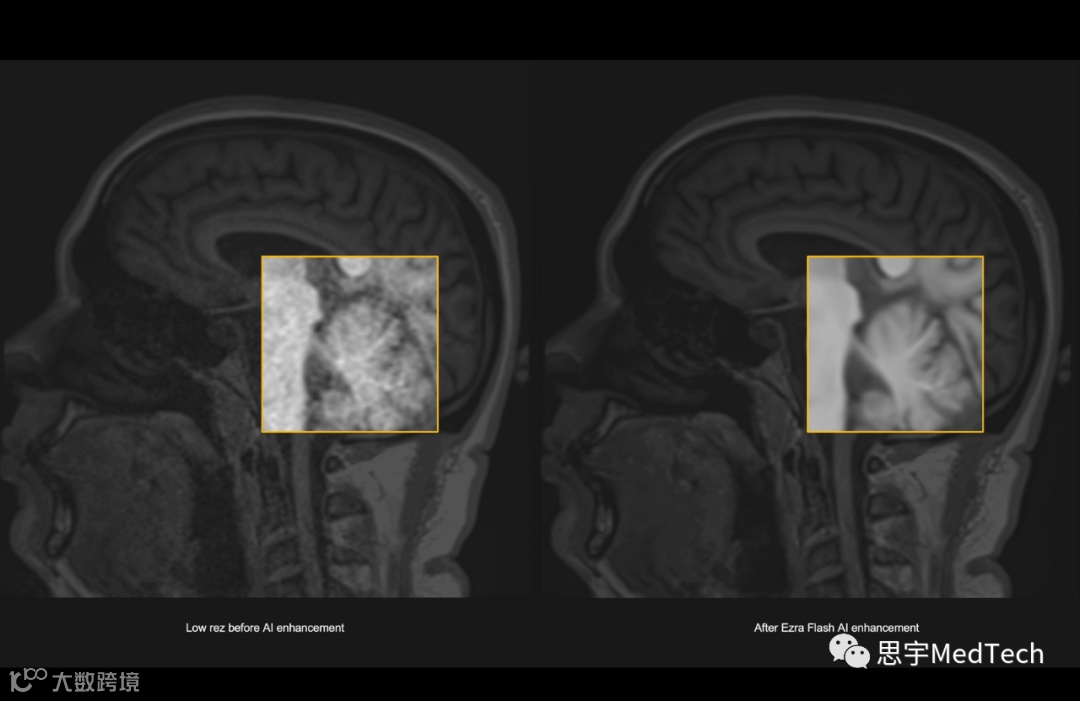

▲(图左为未使用AI技术形成的MRI图像,图右为Ezra Flash AI增强后图像)

纽约大学放射科创新主任兼先进成像创新与研究中心主任Daniel Sodickson博士表示:“Ezra Flash获得FDA批准是一个重要的里程碑——这标志着医学成像使用方式的重大变化。随着时间推移,成像速度逐渐增加已经为患者和医生带来了无数好处。然而,到目前为止,成像主要用于在其他症状已经出现后诊断和表征疾病。”

“相反,Ezra正在将MRI作为一种早期检测癌症的工具,在出现症状之前进行筛查——这种主动监测的安全网以前只对具有某些明确风险因素的患者开放。Ezra Flash将增加早期预警MRI的可及性,并且Ezra随着时间推移重复扫描所产生的数据集将有助于防止假阳性,并确保它提供的警告是适当和可行的。”